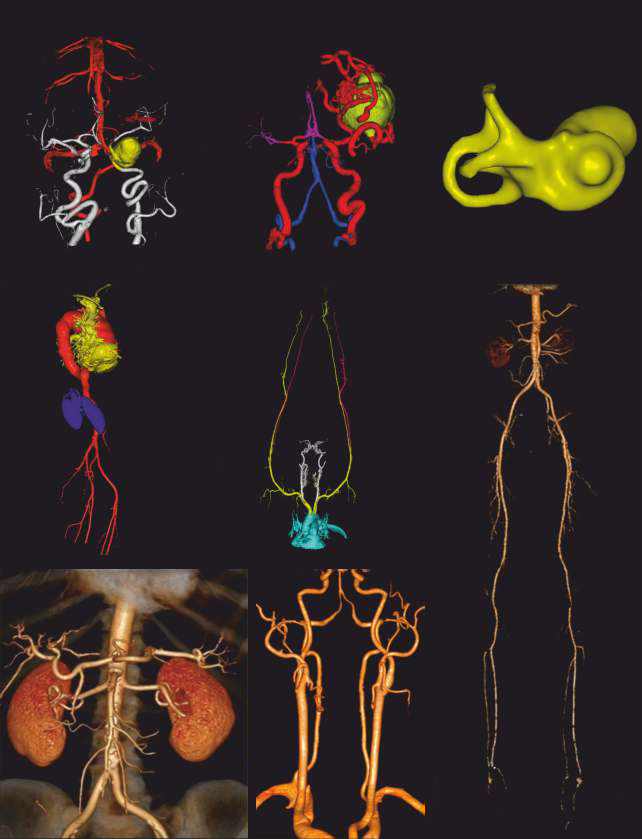

CT Angiography Images

VRT Images